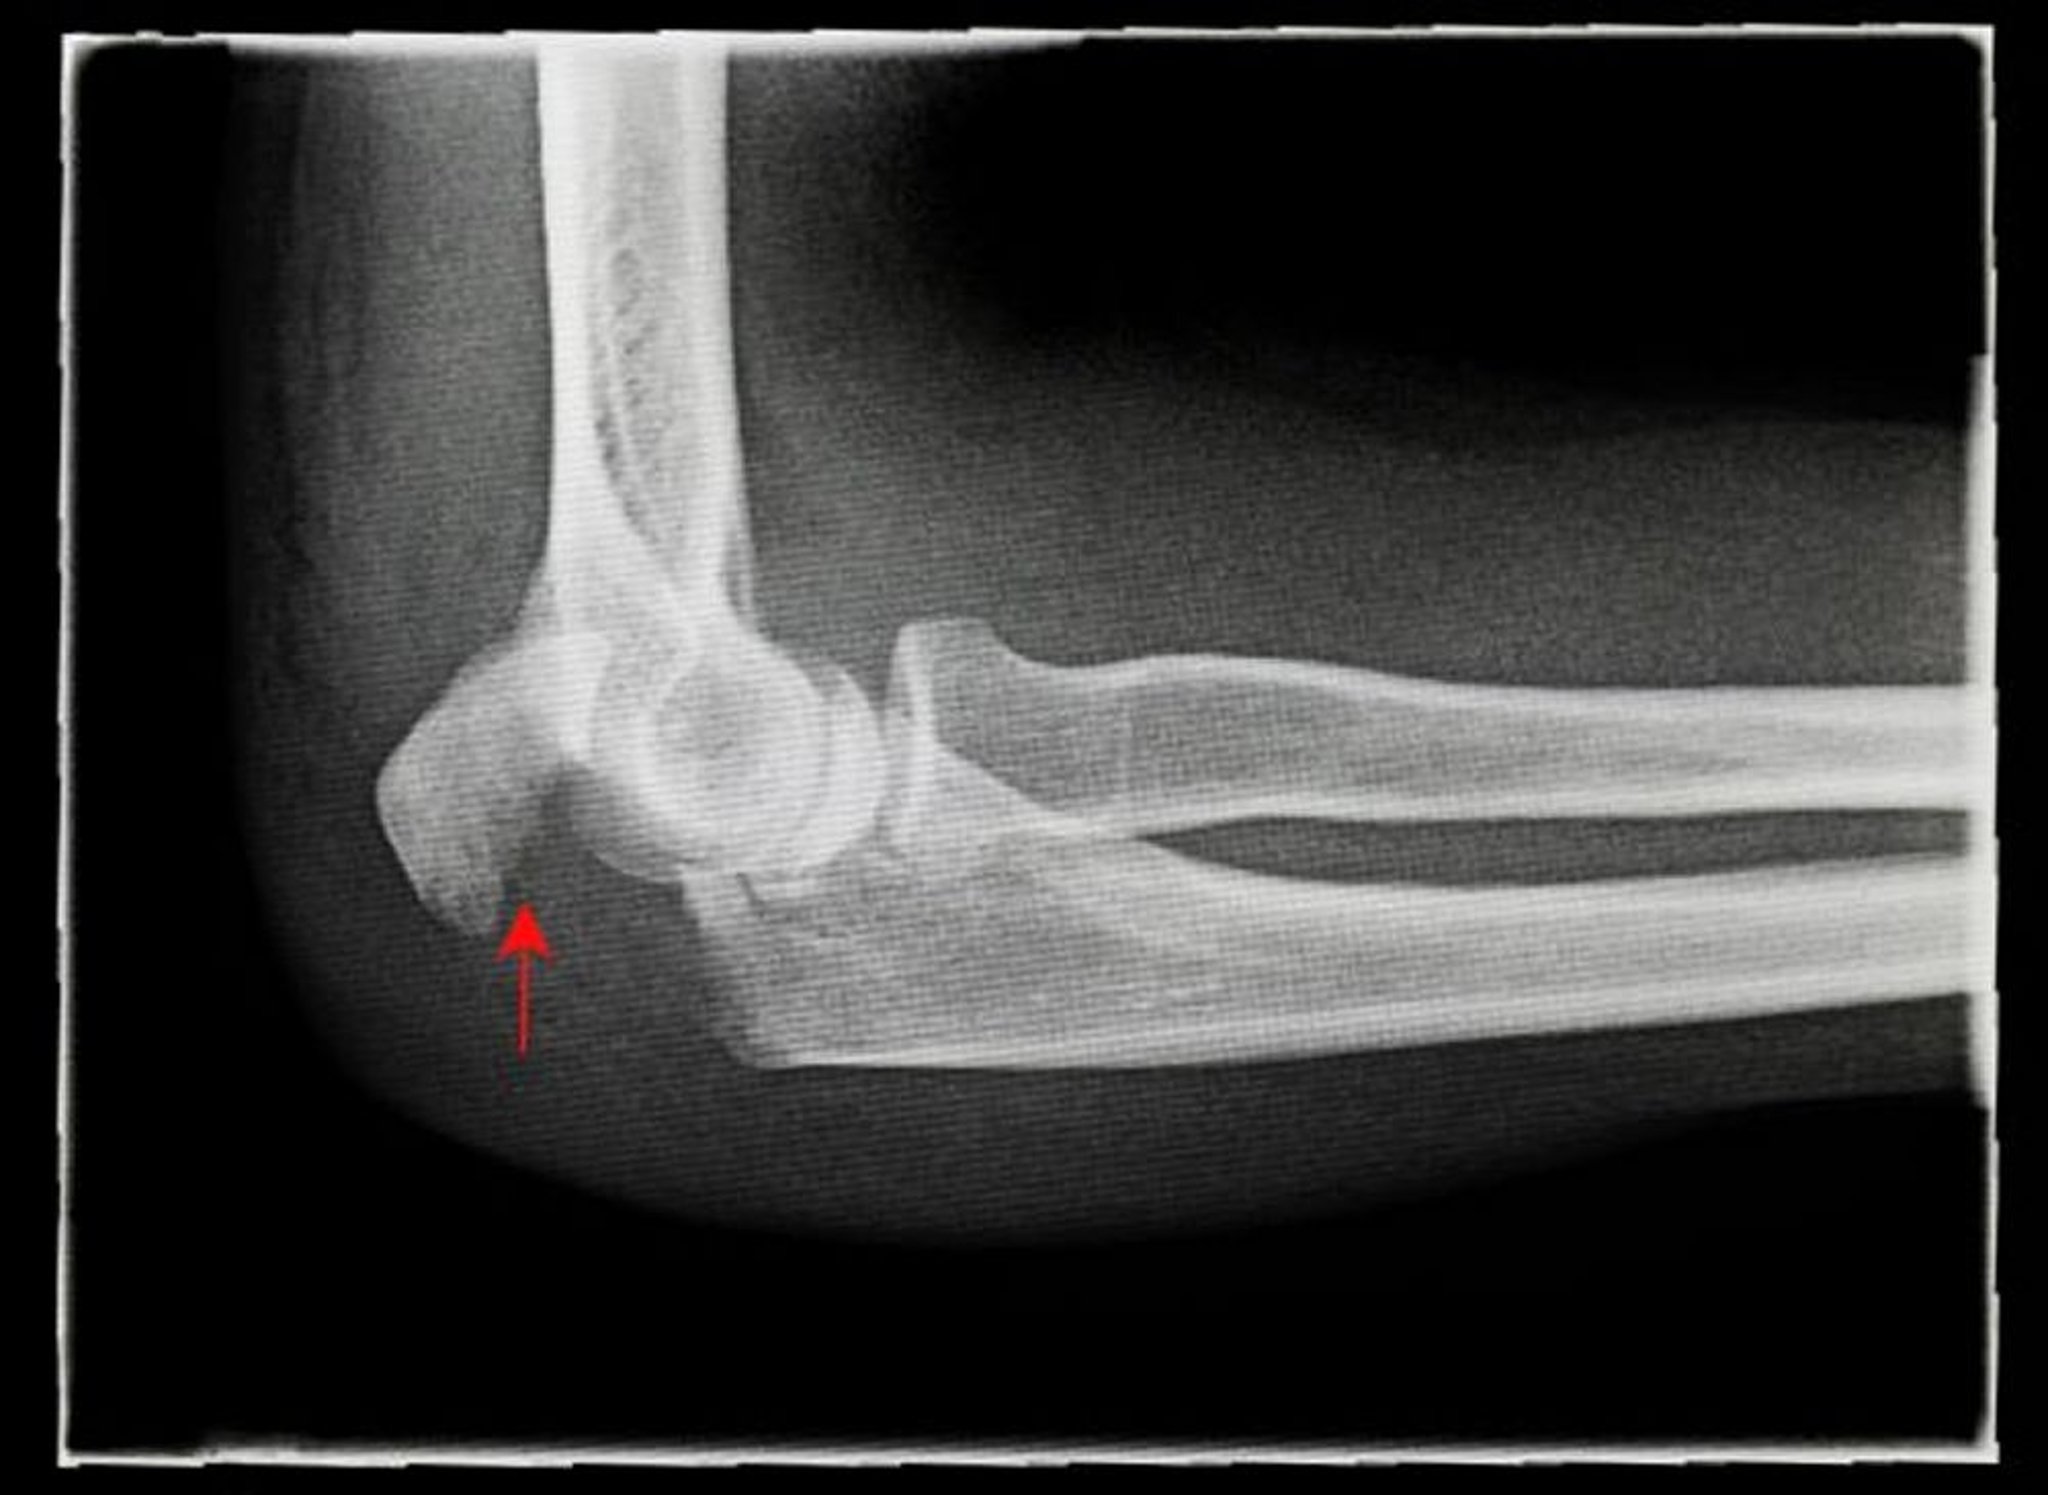

Diese laterale Röntgenaufnahme zeigt eine dislozierte Olekranonfraktur (Pfeil).